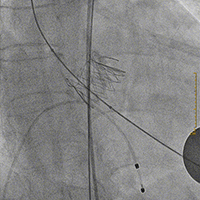

主动脉根部造影,确定瓣环位置

20mm球囊预扩张